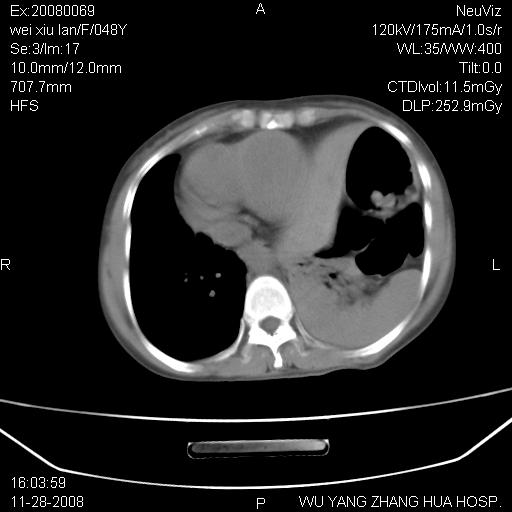

标题: CT16847:女,48岁,咳嗽,发热两日,平常偶有上腹部不适。 [打印本页]

标题: CT16847:女,48岁,咳嗽,发热两日,平常偶有上腹部不适。

能否考虑食管裂孔疝?请老师们多多指教。

这个是左侧膈膨升伴不完全性胃翻转,手术将松弛的左横膈膜折叠缝合即解决问题。

支持左侧膈疝,心脏受压右移.

胃、脾脏及部分肠管明显升高,并压迫心脏移位,

首先考虑:左侧膈疝。

左侧胸腔内见胃肠及脾脏影

支持膈疝

左膈顶及肋膈角均上移,膈面光滑,考虑左膈肌麻痹